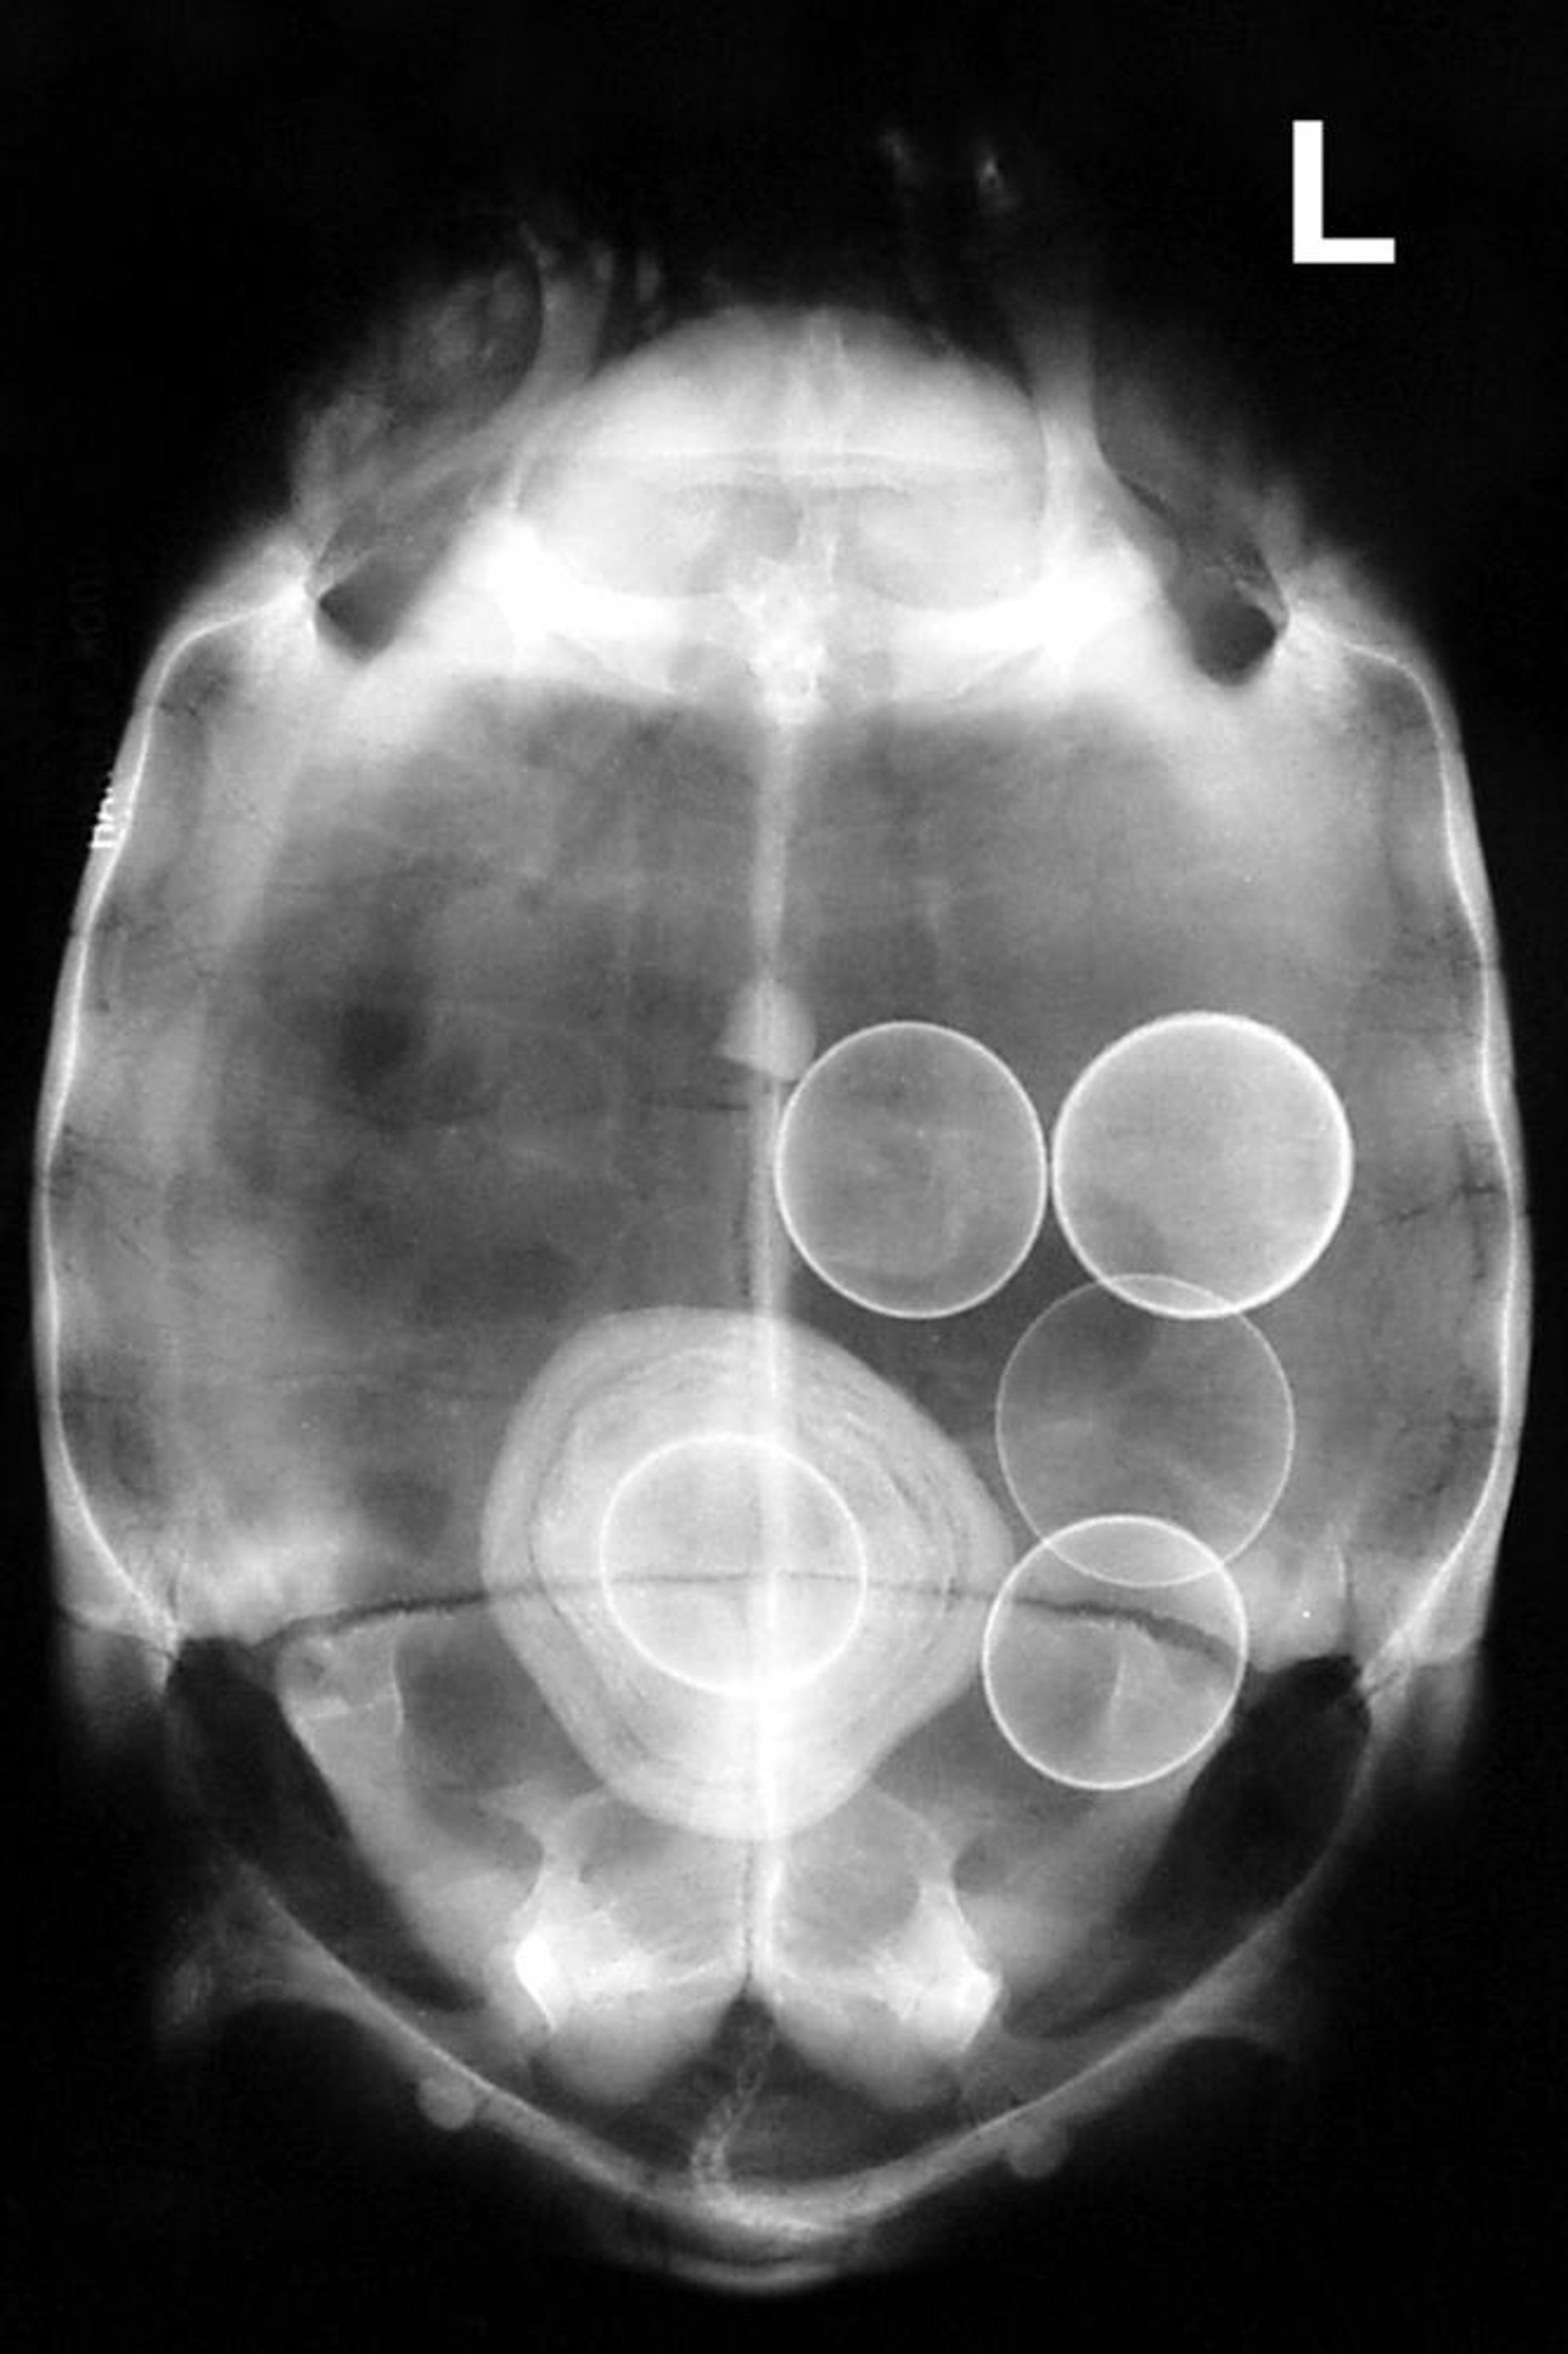

Radiografía de una tortuga griega (Testudo graeca) que muestra varios huevos anómalos, incluido uno dentro de la vejiga y recubierto por ácido úrico, formando un gran urolito.

Cortesía del Dr. Stephen Divers.